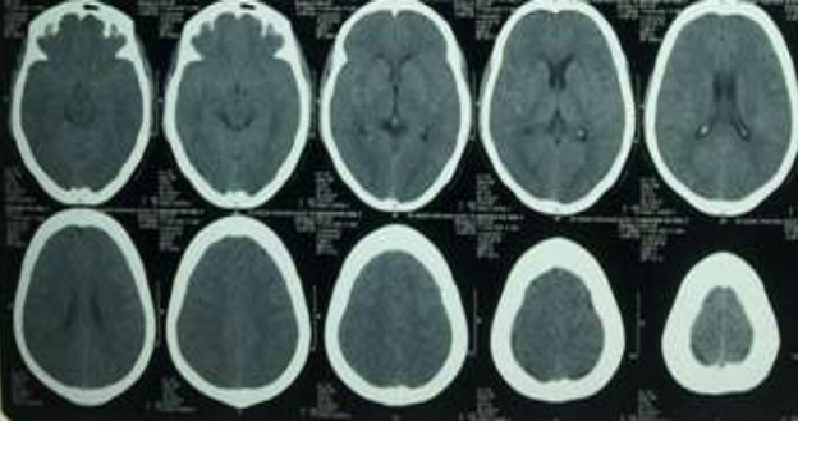

CT đầu không cản quang : bình thường

BN được chỉ định DSA

CTA

Chẩn đoán hình ảnh: 3 túi phình động mạch cảnh trong bên (P) đoạn quanh động mạch mắt.Túi phình 1:2.4x2mm,cổ 2.4mm.Túi phình 2:2.5×2.4mm,cổ 2.2mm.Túi phình 3:3.7x3mm,cổ 3mm. -2 túi phình động mạch cảnh trong bên (T) đoạn quanh động mạch mắt.Túi phĩnh 4:3.4×3.7 mm,cổ 3.4mm.Túi phình 5:3.7×4.3 mm,cổ 3.7 mm. -1 túi phình động mạch đỉnh thân nền : 4×3.7×4.3mm,cổ 3.7 mm.

Chẩn đoán xác định: Xuất huyết dưới nhện do vỡ đa túi phình mạch não

Chụp CT đầu không có thuốc cản quang

CT scan có độ nhạy 90% phát hiện máu trong 24 giờ đầu tiên, độ nhạy 80% vào 3 ngày và độ nhạy 50% sau 1 tuần. CT cũng tốt để đánh giá não úng thủy và các chảy máu nội sọ khác.